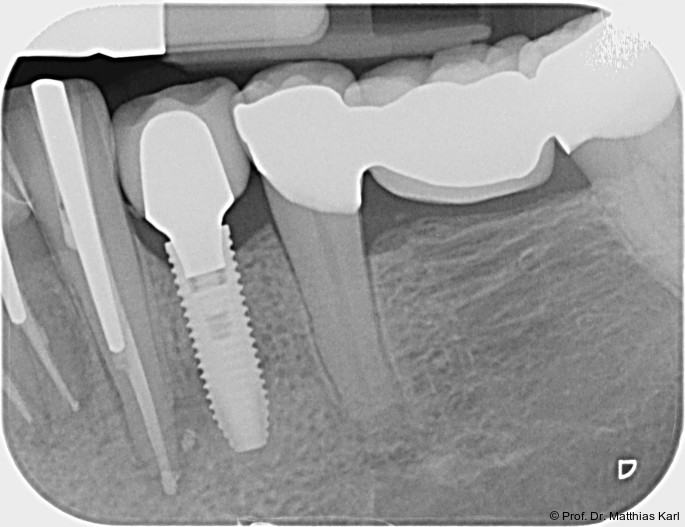

Zur Reduktion der Knochenkompression, insbesondere der bukkal gelegenen Lamelle (Abb. 3), werden derzeit Implantate mit dreieckigem Querschnitt10, 12 sowie Implantate mit zervikal reduziertem Durchmesser16 angeboten. Diese scheinen jedoch im Gegensatz zur subkrestalen Positionierung (Abb. 4a–c) von Implantaten23 keine signifikanten Vorteile zu bieten. Bohrprotokolle, welche sowohl auf das jeweilige Implantatsystem als auch auf die vorliegende Knochenqualität abgestimmt sind, haben ebenfalls das Ziel, zu hohe Einbringdrehmomente zu vermeiden.

Aus prothetischer Sicht ist die Verlässlichkeit der Implantat-Abutment-Verbindung (Abb. 5), die einer hinreichenden Dauerfestigkeit unter Wechsellast bedarf, entscheidend. Kritisch ist hier das Erreichen von Wandstärke im Implantatkörper, welcher zudem die Verbindungsgeometrie und die Abutmentschraube aufnehmen muss. Häufig wird daher die zervikale Außengeometrie dentaler Implantate an die Notwendigkeiten der Innenverbindung angepasst, was zu flacheren, nicht schneidenden Außengewinden führt, wohingegen aus knochenphysiologischer Sicht im zervikalen Implantatanteil schneidende, tiefe Gewindegänge vorteilhafter wären, um dem härteren, kortikalen Knochen zu begegnen.